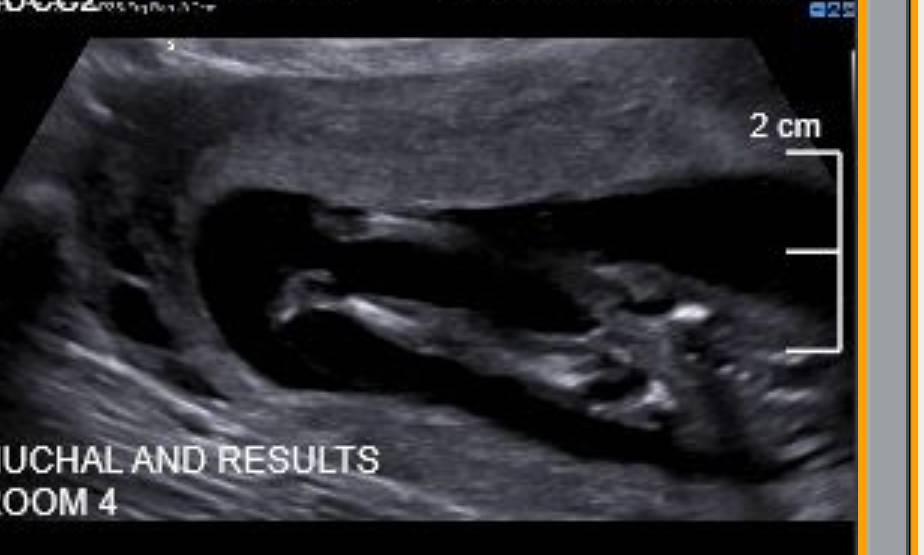

Hi all, the ultrasound technician wouldn't tell me what she thought - am dying to know. Please help!! Attachment 42099Attachment 42100Attachment 42101Attachment 42103